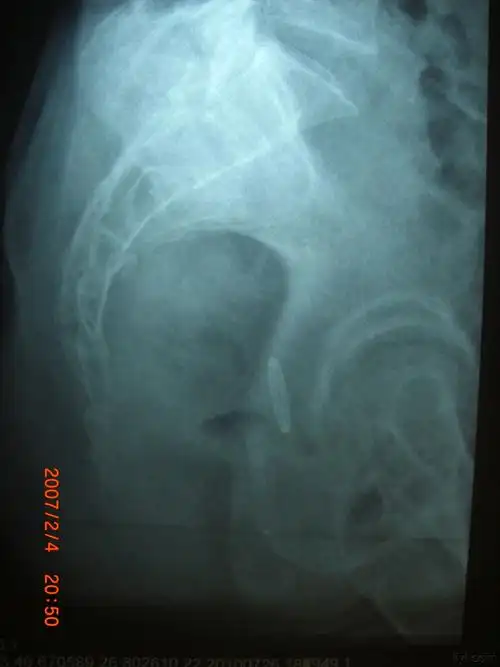

摔了一跤怀疑尾骨骨折或骨裂,去拍了片子遇到个庸医

【读片】骶尾椎ct [病例帖]

医影精品尾骨创伤及尾骨疼痛的影像学表现